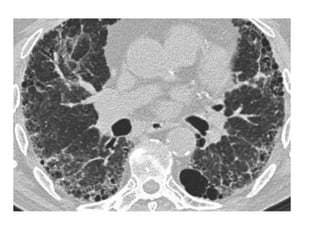

49-year-old woman with persistent and progressive cough, dyspnea, and hypoxemia,

prompting biopsy of her lungs, which revealed chronic desquamative interstitial

pneumonia (DIP) related to extensive cigarette smoking history, CT images through

mid and lower lungs show patchy ground-glass opacities in all lobes of both lungs

with peripheral predilection accompanied by lower lobe bronchial wall thickening, note

small cysts scattered mostly in right lung in regions of ground-glass attenuation,

finding that can occur in DIP